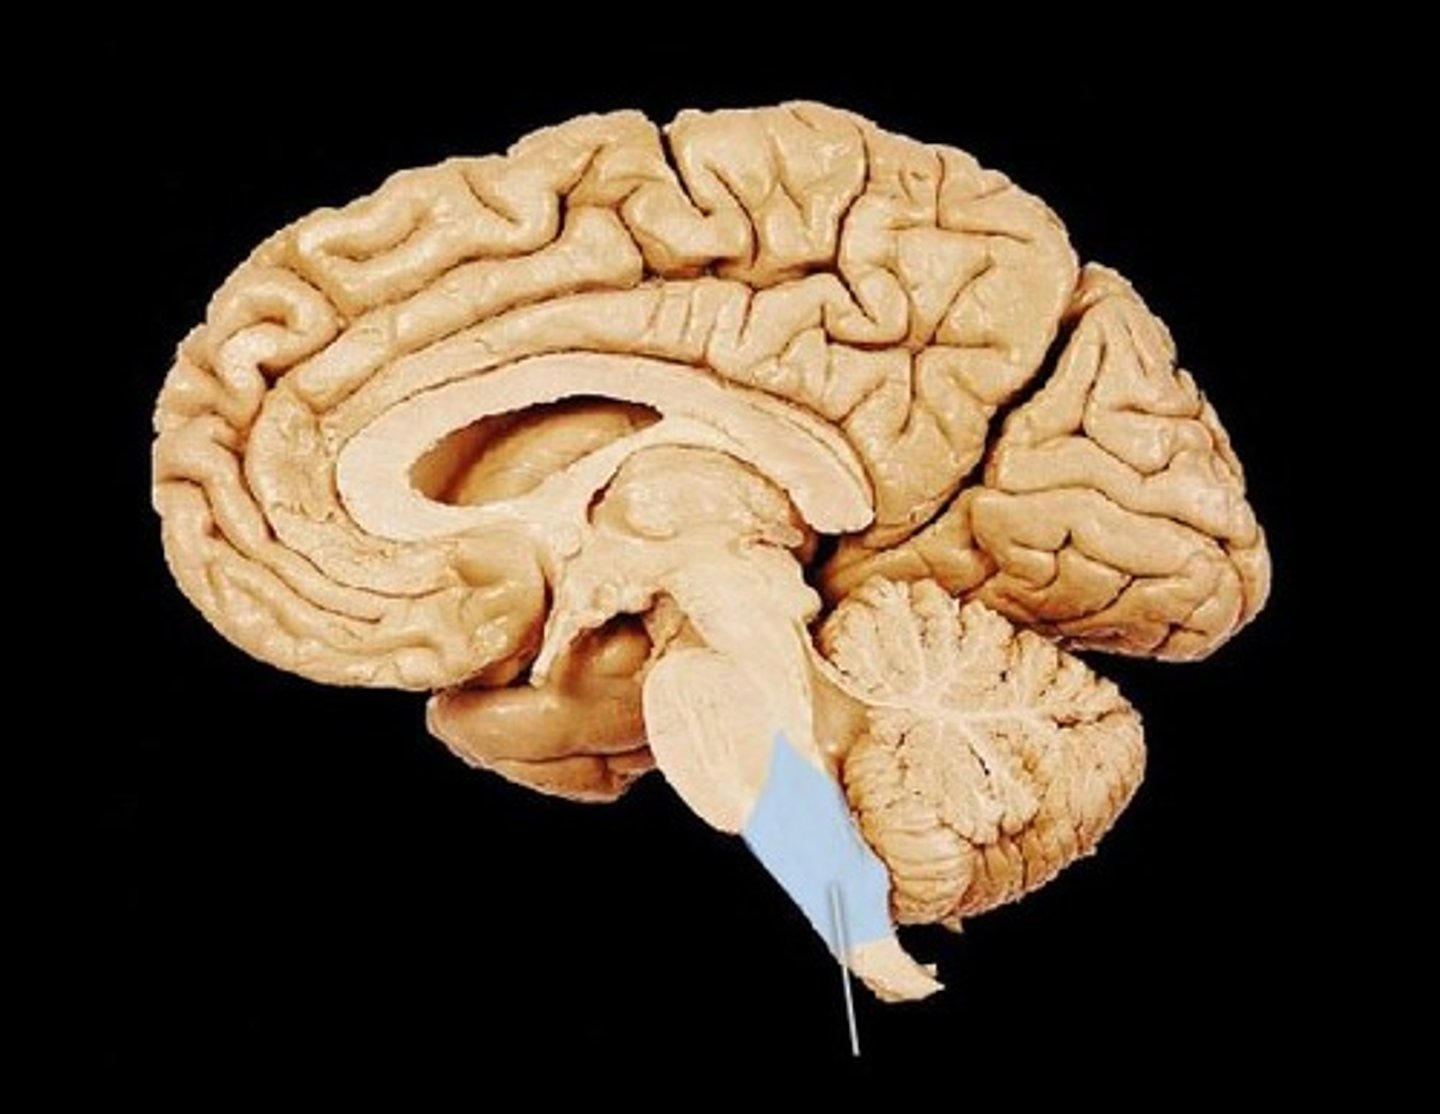

Pons

Part of the brain stem which connects parts of the nervous system, helps with movement